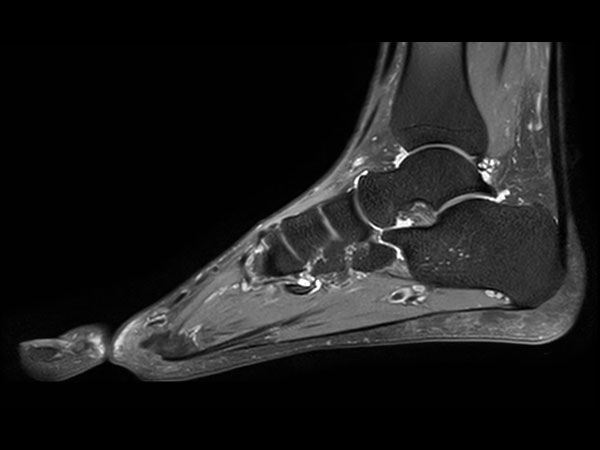

Ankle imaging with the dS 16ch FootAnkle coil

• Clinical Application